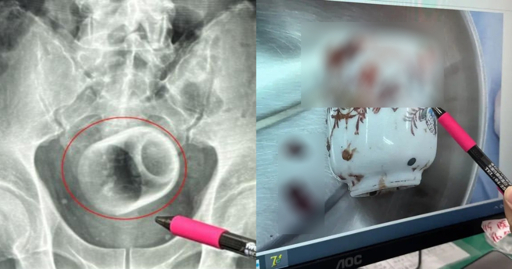

schizoidman@lemmy.zip to Not The Onion@lemmy.worldEnglish · 10 days agoMan in Taiwan somehow gets 8cm by 6cm ceramic cup in bottom, claims it got there 'by accident'mothership.sgexternal-linkmessage-square50linkfedilinkarrow-up1227arrow-down18

arrow-up1219arrow-down1external-linkMan in Taiwan somehow gets 8cm by 6cm ceramic cup in bottom, claims it got there 'by accident'mothership.sgschizoidman@lemmy.zip to Not The Onion@lemmy.worldEnglish · 10 days agomessage-square50linkfedilink